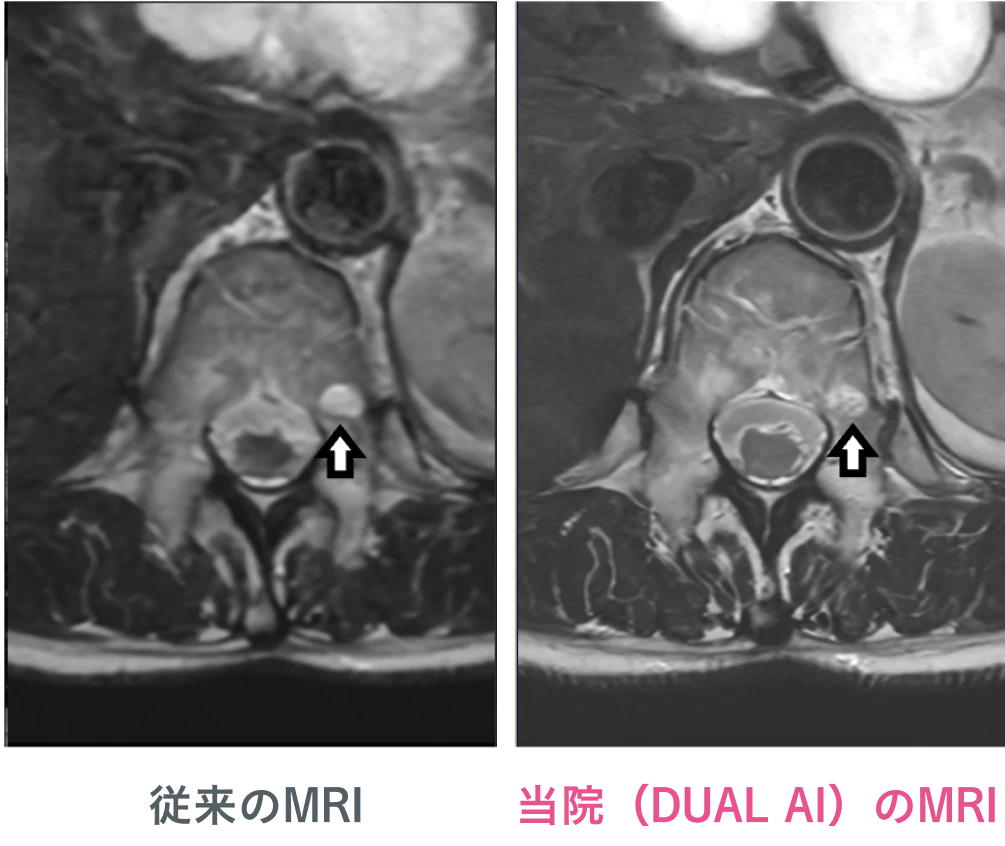

当院のMRIは、すでにAIが入っていましたが、日本初の施設として、2025年10月より、「DUAL AI (Precise)」※ を導入しました。

これは従来のAIを二重にして、「超解像」まで可能にしたもので、検査時間をさらに短縮しながら、ノイズを徹底的に除去し、画像の鮮明さ(高精細化)を飛躍的に向上させます。

これにより、受診者様の負担(閉所感や検査音など)を最小限に抑えつつ、これまで以上に微細な病変の発見が期待できる、より高精度な診断を実現します。

脊椎MRIでの比較

当院のMRIは、より滑らかで、ノイズが少ない画像が撮影できます。腫瘍内部の微細な性状が明瞭に描出されています。